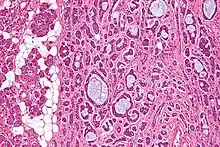

| Micrograph of an adenoid cystic carcinoma of a salivary gland (right of image): Normal serous glands, typical of the parotid gland, are also seen (left of image), H&E stain. | |